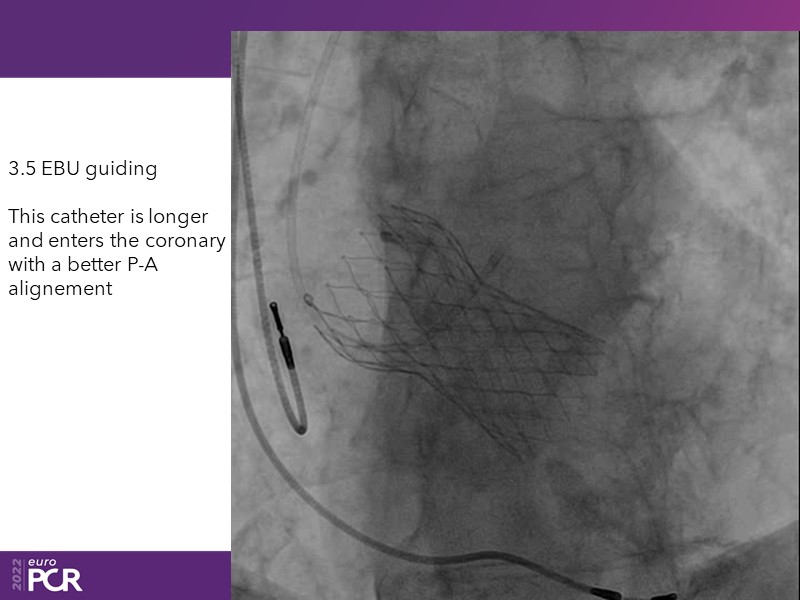

Consult this session to learn how to contribute to streamlined pre- and post-TAVI patient pathways, to discover updates on the optimised TAVI procedure and appreciate the variances in different valve designs and the long-term patient outcomes, as well as to discuss the right time of PCI in TAVI patients (steps on the procedure).